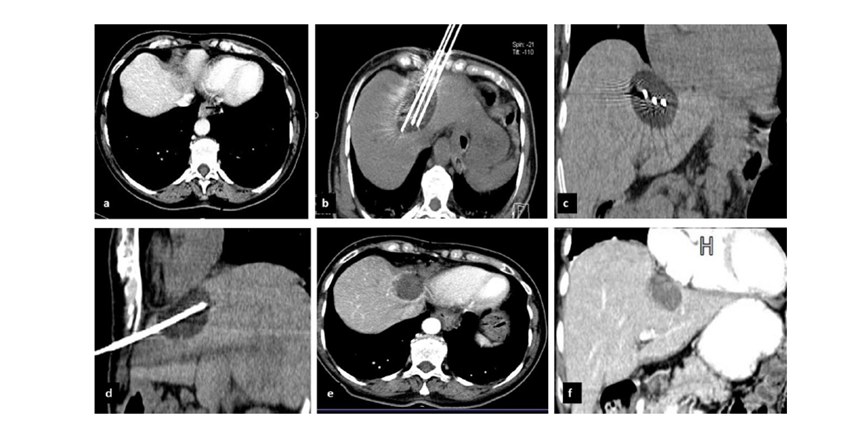

冷凍消融治療的路徑有經皮、腹腔鏡及開腹3 種方式,臨床常用影像引導經皮入路。本共識規(guī)范了影像引導下肝癌冷凍消融治療的患者選擇和技術操作流程,提高治療效果、減少手術風險性,為臨床實踐和規(guī)范肝癌的冷凍消融治療提供參考。本文將對該專家共識的關鍵內容進行簡述。

(1)設計進針路徑時,應注意避開肋骨、胃、腸及膽囊等結構,避免術中冷凍能量沿探針傳遞損傷空腔臟器,導致膽瘺及腸瘺;

(2)如果冷凍治療應用CT 或MRI 進行術中引導及監(jiān)控,則術前應鍛煉患者呼吸配合,每次掃描時屏氣幅度一致,平靜呼氣末屏氣最常應用;

(3)包膜下肝癌,穿刺路徑設計應經過部分正常的肝組織,減少腫瘤破裂出血及腹腔內播散的機會;

(4)治療近膈頂的肝癌,盡可能經肋膈角下方進針,避免探針經過肋膈角、膈肌,損傷肺組織,且冷凍過程中注意控制消融范圍,必要時采取水隔離技術,勿傷及膈肌;

(5)靠近腹壁的病灶進行冷凍治療,應在體表穿刺點敷溫水囊,避免凍傷腹壁和皮膚;

(6)靠近膽囊及胃腸道的病變冷凍治療時,術中監(jiān)控病變,使冷凍冰球外緣勿達到膽囊和胃腸,防止凍傷后穿孔;

(7)靠近大血管的病變進行手術時,需應用較多數目的冷凍探針,因大血管能夠迅速帶走冷凍能量,使形成的冷凍冰球較小,影響治療效果;

(8)直徑3 ~ 5cm 但影像學檢查顯示邊界不清呈浸潤性生長的病灶,冷凍消融范圍應相應擴大,超過病變顯示范圍1.5cm 以上;

(9)直徑> 5cm 的病灶,可通過多針穿刺和多點布針的方法盡可能適形、全面地消融病灶,也可根據情況行姑息性治療,部分滅活腫瘤、減輕腫瘤負荷或延緩病情進展,以延長患者生存時間和提高生存質量。